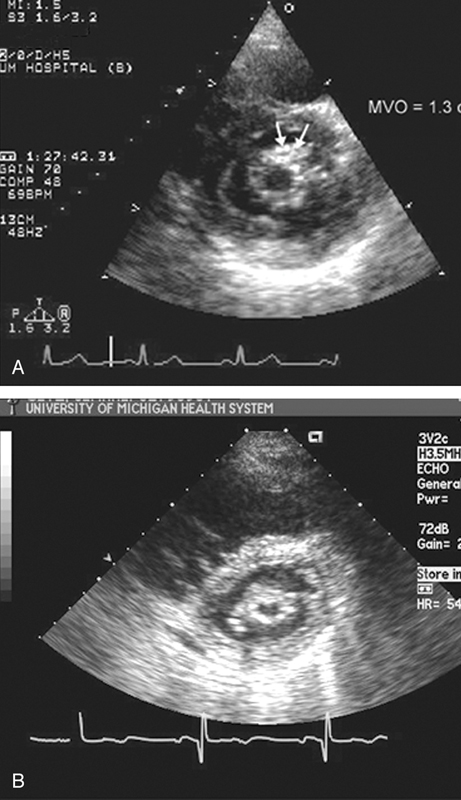

فحوصات تشخيصية لبعض امراض القلب والشرايين التاجية